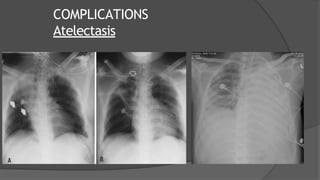

COMPLICATIONS

Lungs Atelectasis

Microatelectasis

May not be apparent on Xray

Intrapulmonary shunt → hypoxemia

Lobar /Panlobar Atelectasis

○ Mucus plug

○ Foreign body

○ Intubation of main bronchus

Atelectasis